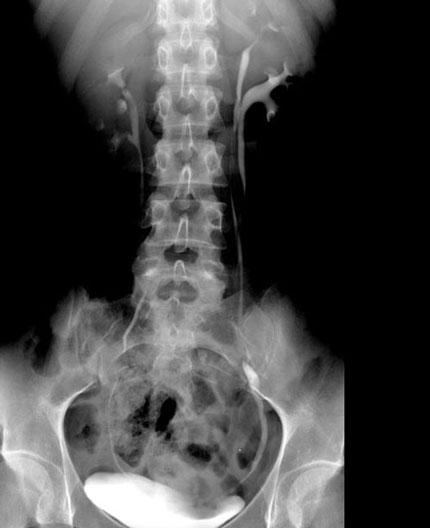

Kidney, Double Ureter

1. Ureter #1

2. Ureter #2